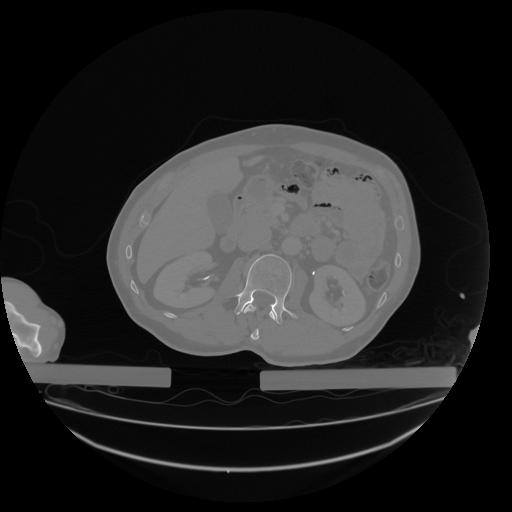

34 CUERPO,CE,Vol,1.0,CUERPO,,